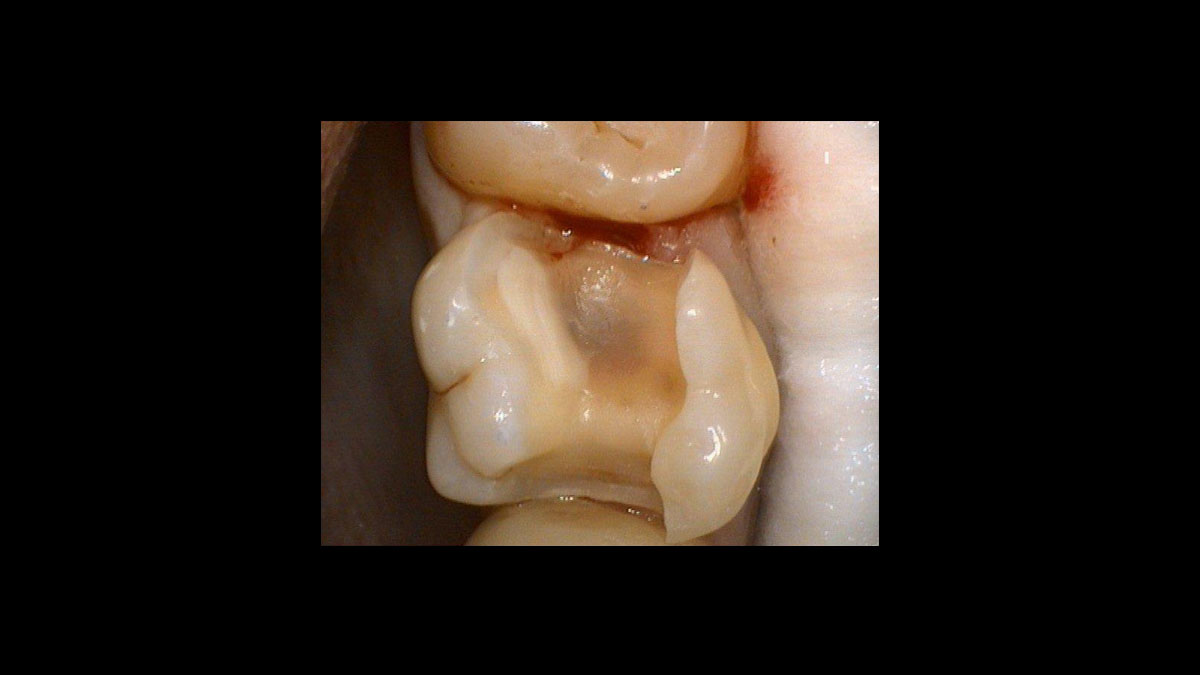

Operculectomie